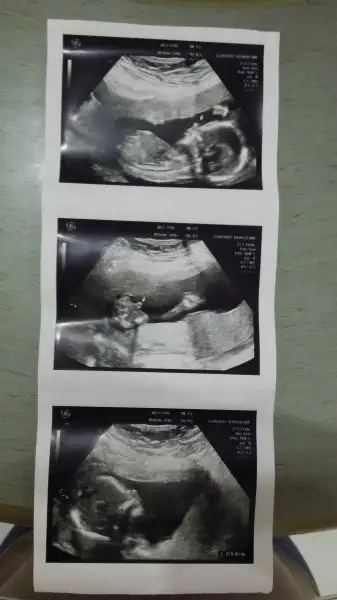

merhaba arkadaşlar benim görüntüde solda duruyor kap atışının olduğu yeri doktor işaretlemişti

merhabalar arkadaşlar 12 hafta 6 günlük olduk cinsiyet söylemedi doktorumuz 16. haftada dedi tahmni olan var mı?